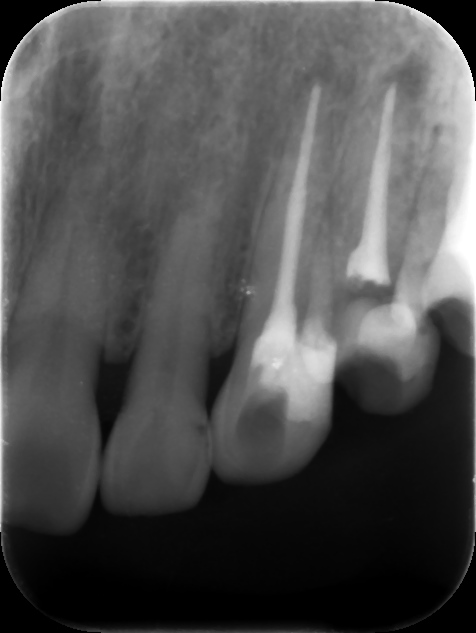

初診時レントゲン。他院で1年以上かけて根管治療を行っているが痛みや歯茎の腫れが引かずに来院。元々は歯髄が生きていた生活歯の抜髄を行ったケース(イニシャルトリート)。同時に3本もの歯を抜髄して長期に根管治療を行う診断に問題があると言わざるを得ない。患者さんは心身ともに疲弊し、歯科治療への不信が高まってしまうのも無理はない。まずは、現状の説明と解決策を提示し、歯科治療への不安を取り除くところから治療が始める。